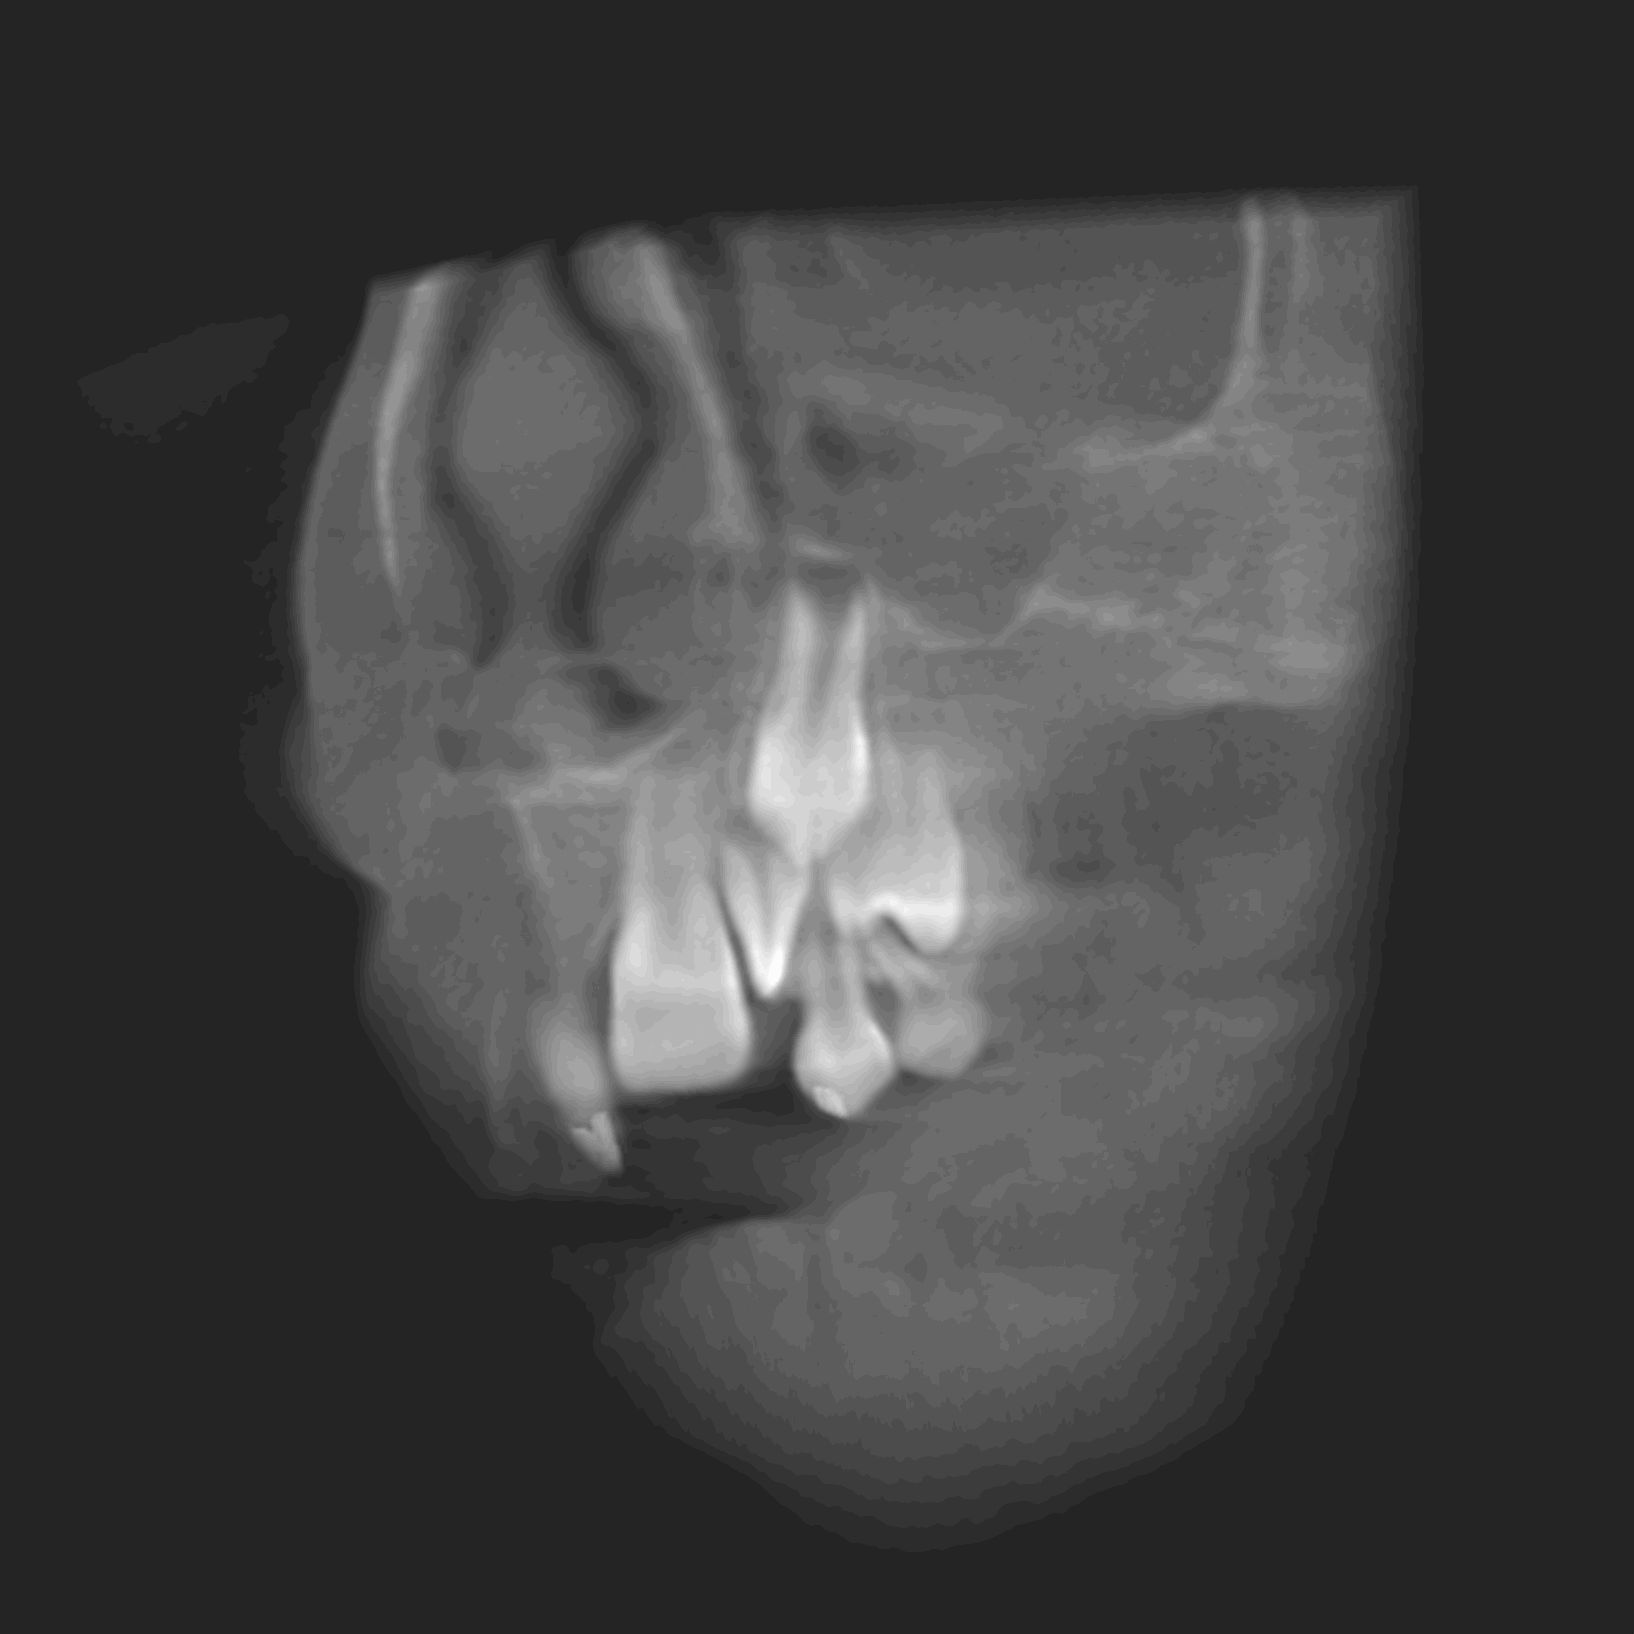

Le cone beam est une nouvelle technique de radiographie numérisée situé entre le panoramique dentaire et le scanner, il utilise un faisceau d’irradiation de forme conique d'où son nom. Cet appareil présente notamment l’avantage d’être plus précis que le panoramique dentaire et il possède une résolution similaire, voire supérieure à celle du scanner, avec en plus la possibilité d’une reconstruction numérique en 3D.

Le cone beam utilisé en pathologie dentaire et maxillo-faciale est indiqué pour l’examen des tissus minéralisés (dents, cartilages, os), il permet d’identifier les lésions osseuses, les fractures, les infections, les kystes ou les corps étrangers.

Il évalue au plus juste le volume osseux et la position des structures anatomiques comme les nerfs en vue de la pose d’implants. La modélisation en 3D permet la taille et la forme des implants proportionnellement à la morphologie du patient et de simuler virtuellement leurs emplacements.

Les applications du cone beam dentaire sont donc nombreuses allant de la chirurgie buccale à l’orthodontie (télécrânes...), en passant par la chirurgie maxillo-faciale et l’ORL.

- pathologie des sinus maxillaires